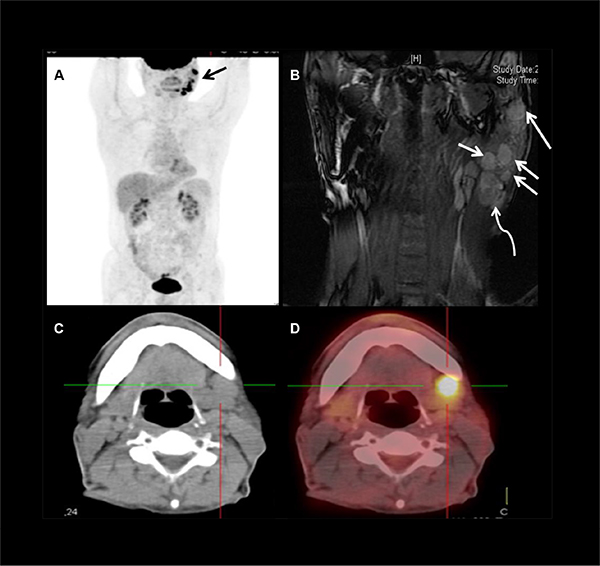

Figure 1: Images showing level Ib and level VIII nodes metastases in a 58 years old male patient with LELC of the left parotid gland. (A) PET panorama demonstrated multiple nodules (arrow) in the left parotid and upper neck with high uptake of FDG. (B) Coronal MRI showed multiple metastases (arrows) in and just beneath (curved arrow) the left parotid. (C and D) CT-PET suggested level Ib nodal involvement.

Level VIII: The highest incidence of nodal metastases was in level VIII, 37 (88.1%) patients had positive nodes in this area (Figure 1A and 1B). Metastases in this area could be solitary, or multiple, or accompanied with lymphadenopathy in other levels.

Level I: No solitary metastasis to level Ib was found. Of the 6 patients with level Ib node involvement (Figure 1C and 1D), all were accompanied with both level II and level VIII lymphadenopathy. But none had nodal disease at level Ia.